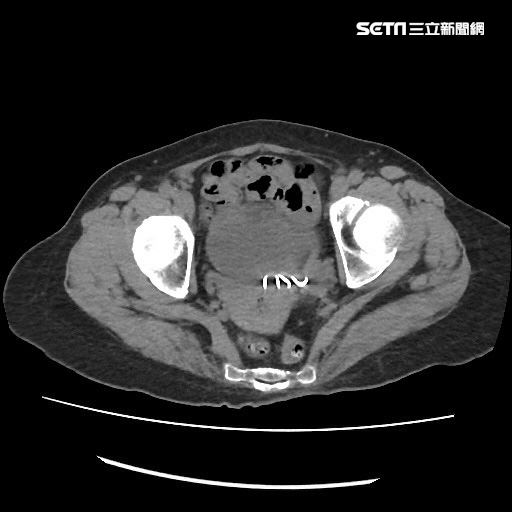

經進一步安排檢查後,果不其然,從該男的膀胱灌藥進去的時候,會發現膀胱裡面有一個小洞,藥劑可以跑到他的直腸裡,這就能理解他為什麼會有失禁的狀況。因為當膀胱脹起來的時候,裡面有幾百CC的尿液,而這些尿液灌到腸子裡,就會有失禁的情形。

所幸,陳榮堅說後來就幫該男安排手術。開刀時發現該男在乙狀結腸跟膀胱有一個廔管,將那段截開,並且切除部分壞掉的腸子,後來這位病人的問題就完整解決了。